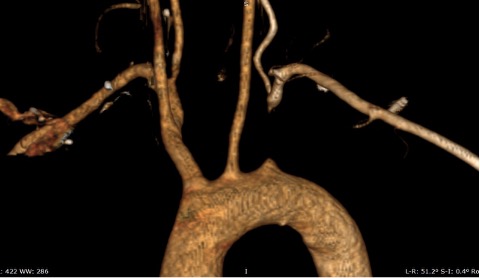

Relevant Test Results Prior to Catheterization

Duplex ultrasonography showed monophasic waveform in the left axillary, brachial, radial, and ulnar arteries. Retrograde flow was observed at the left vertebral artery, findings consistent with left subclavian steal syndrome. Computed Tomography Angiography (CTA) showed non calcified plaque with total occlusion from ostial left subclavian artery up to just before the origin of vertebral artery, with a tapered distal segment, and approximately 25–26 mm in length.